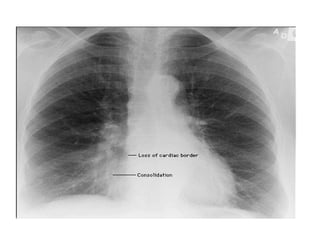

Finally, Check the Lung Fields

• Infiltrates

• Increased interstitial markings

• Masses

• Absence of normal margins

• Air bronchograms

• Increased vascularity

Chest x ray